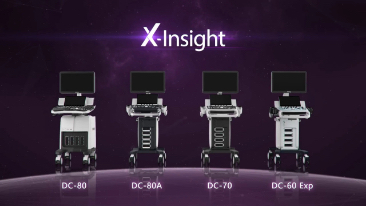

DC-60 Exp

X-Insight, daha geli?mi? g?rĂŒntĂŒler elde etmek i?in kapsaml? bir ??zĂŒmdĂŒr.

Mindrayâin yeni ??zĂŒmĂŒ, geli?en en yeni ultrason teknolojileri ile birlikte, mĂŒ?terilerin g?rĂŒ?lerini klinik gerekliliklerle tam anlam?yla birle?tiren bir ??zĂŒmdĂŒr. Taptaze bir ruhla, gelece?e odaklanarak ve s?n?rs?zl???n pe?inde ko?arak, artan ?l?eklenebilirlikte sĂŒrekli olarak geli?en bir ??zĂŒmdĂŒr.

?ok y?nlĂŒ bir partner olarak, X-Insight'l? DC-60 Exp, her y?nĂŒyle gĂŒnlĂŒk klinik uygulamay? kolayl?kla ve belirsizlik olmadan y?netmenize yard?mc? olacak kapsaml? bir ??zĂŒm sunar.

MĂŒ?teri gereksinimlerine y?nelik g?rĂŒ?ler temelinde, X-Insight'l? DC-60 Exp, eXpress Clarity, eXceptional Intelligence ve eXceeding Experience ile gĂŒ?lendirilerek, hassas g?rĂŒntĂŒlemeyle yĂŒksek verimlilik sa?layacak ?ekilde tasarlanm??t?r.